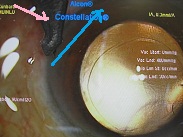

黄斑円孔の手術に関しては、?で記載しましたが、簡単におさらいすると、目の中に器械をいれて、内境界膜という網膜の表層の膜を剥離し、網膜を柔らかくします。その後、目の中に空気を入れてうつ伏せをすることで、円孔の周囲の網膜を浮力で引き寄せて、穴を閉じる。という方法です。

ここで重要なのですが、手術は、

なくなってしまった中心部(黄斑部)の網膜を元に戻すのではありません。

周りの網膜を引き寄せて、穴を閉じ、中心部の網膜の代役をさせるのです。